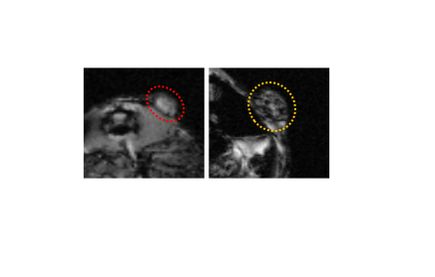

Iron oxide nanoparticles — the tiny particles about 1/1000th the size of a speck of dust — were injected intravenously into mice to locate lesions; they accumulated in the tissue lesions, enabling them to be identified by imaging.

The mice were injected with a low dose of nanoparticles that had been modified with a peptide specially designed to target a receptor that is abundant in endometriosis cells. By targeting that receptor, the nanoparticles were able to locate and accumulate in the lesions.

With the nanoparticles acting as a contrast agent spotlighting the lesions, OHSU radiologists Khashayar Farsad, M.D., Ph.D., associate professor of interventional radiology in the OHSU School of Medicine, and Cory Wyatt, Ph.D., research assistant professor of diagnostic radiology in the OHSU School of Medicine, were able to effectively image the lesions.

“Nanoparticle technology holds promise as a future molecular imaging tool in the diagnosis of many conditions, including endometriosis,” Farsad said. “Currently, small lesions are identified by direct visualization during surgery. Although very preliminary, this proof-of-concept study shows how nanotechnology could provide a novel non-invasive method to identify and potentially treat these lesions.”